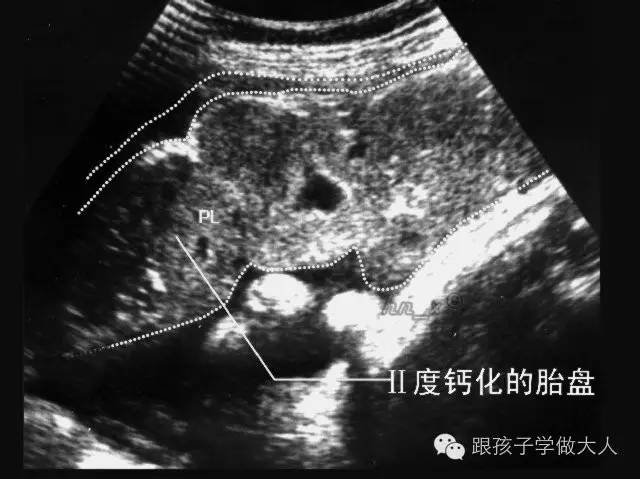

胎盘是有一定寿命的,预产期过后的两周,胎盘的功能开始减退,造成输氧不够,使胎儿经常处于缺氧态势。过期妊娠的胎盘,在胎儿娩出时常比正常胎盘要小,表面散有白色斑纹,有时还可以看到坚硬如石的钙化点,这就是胎盘老化的症状。